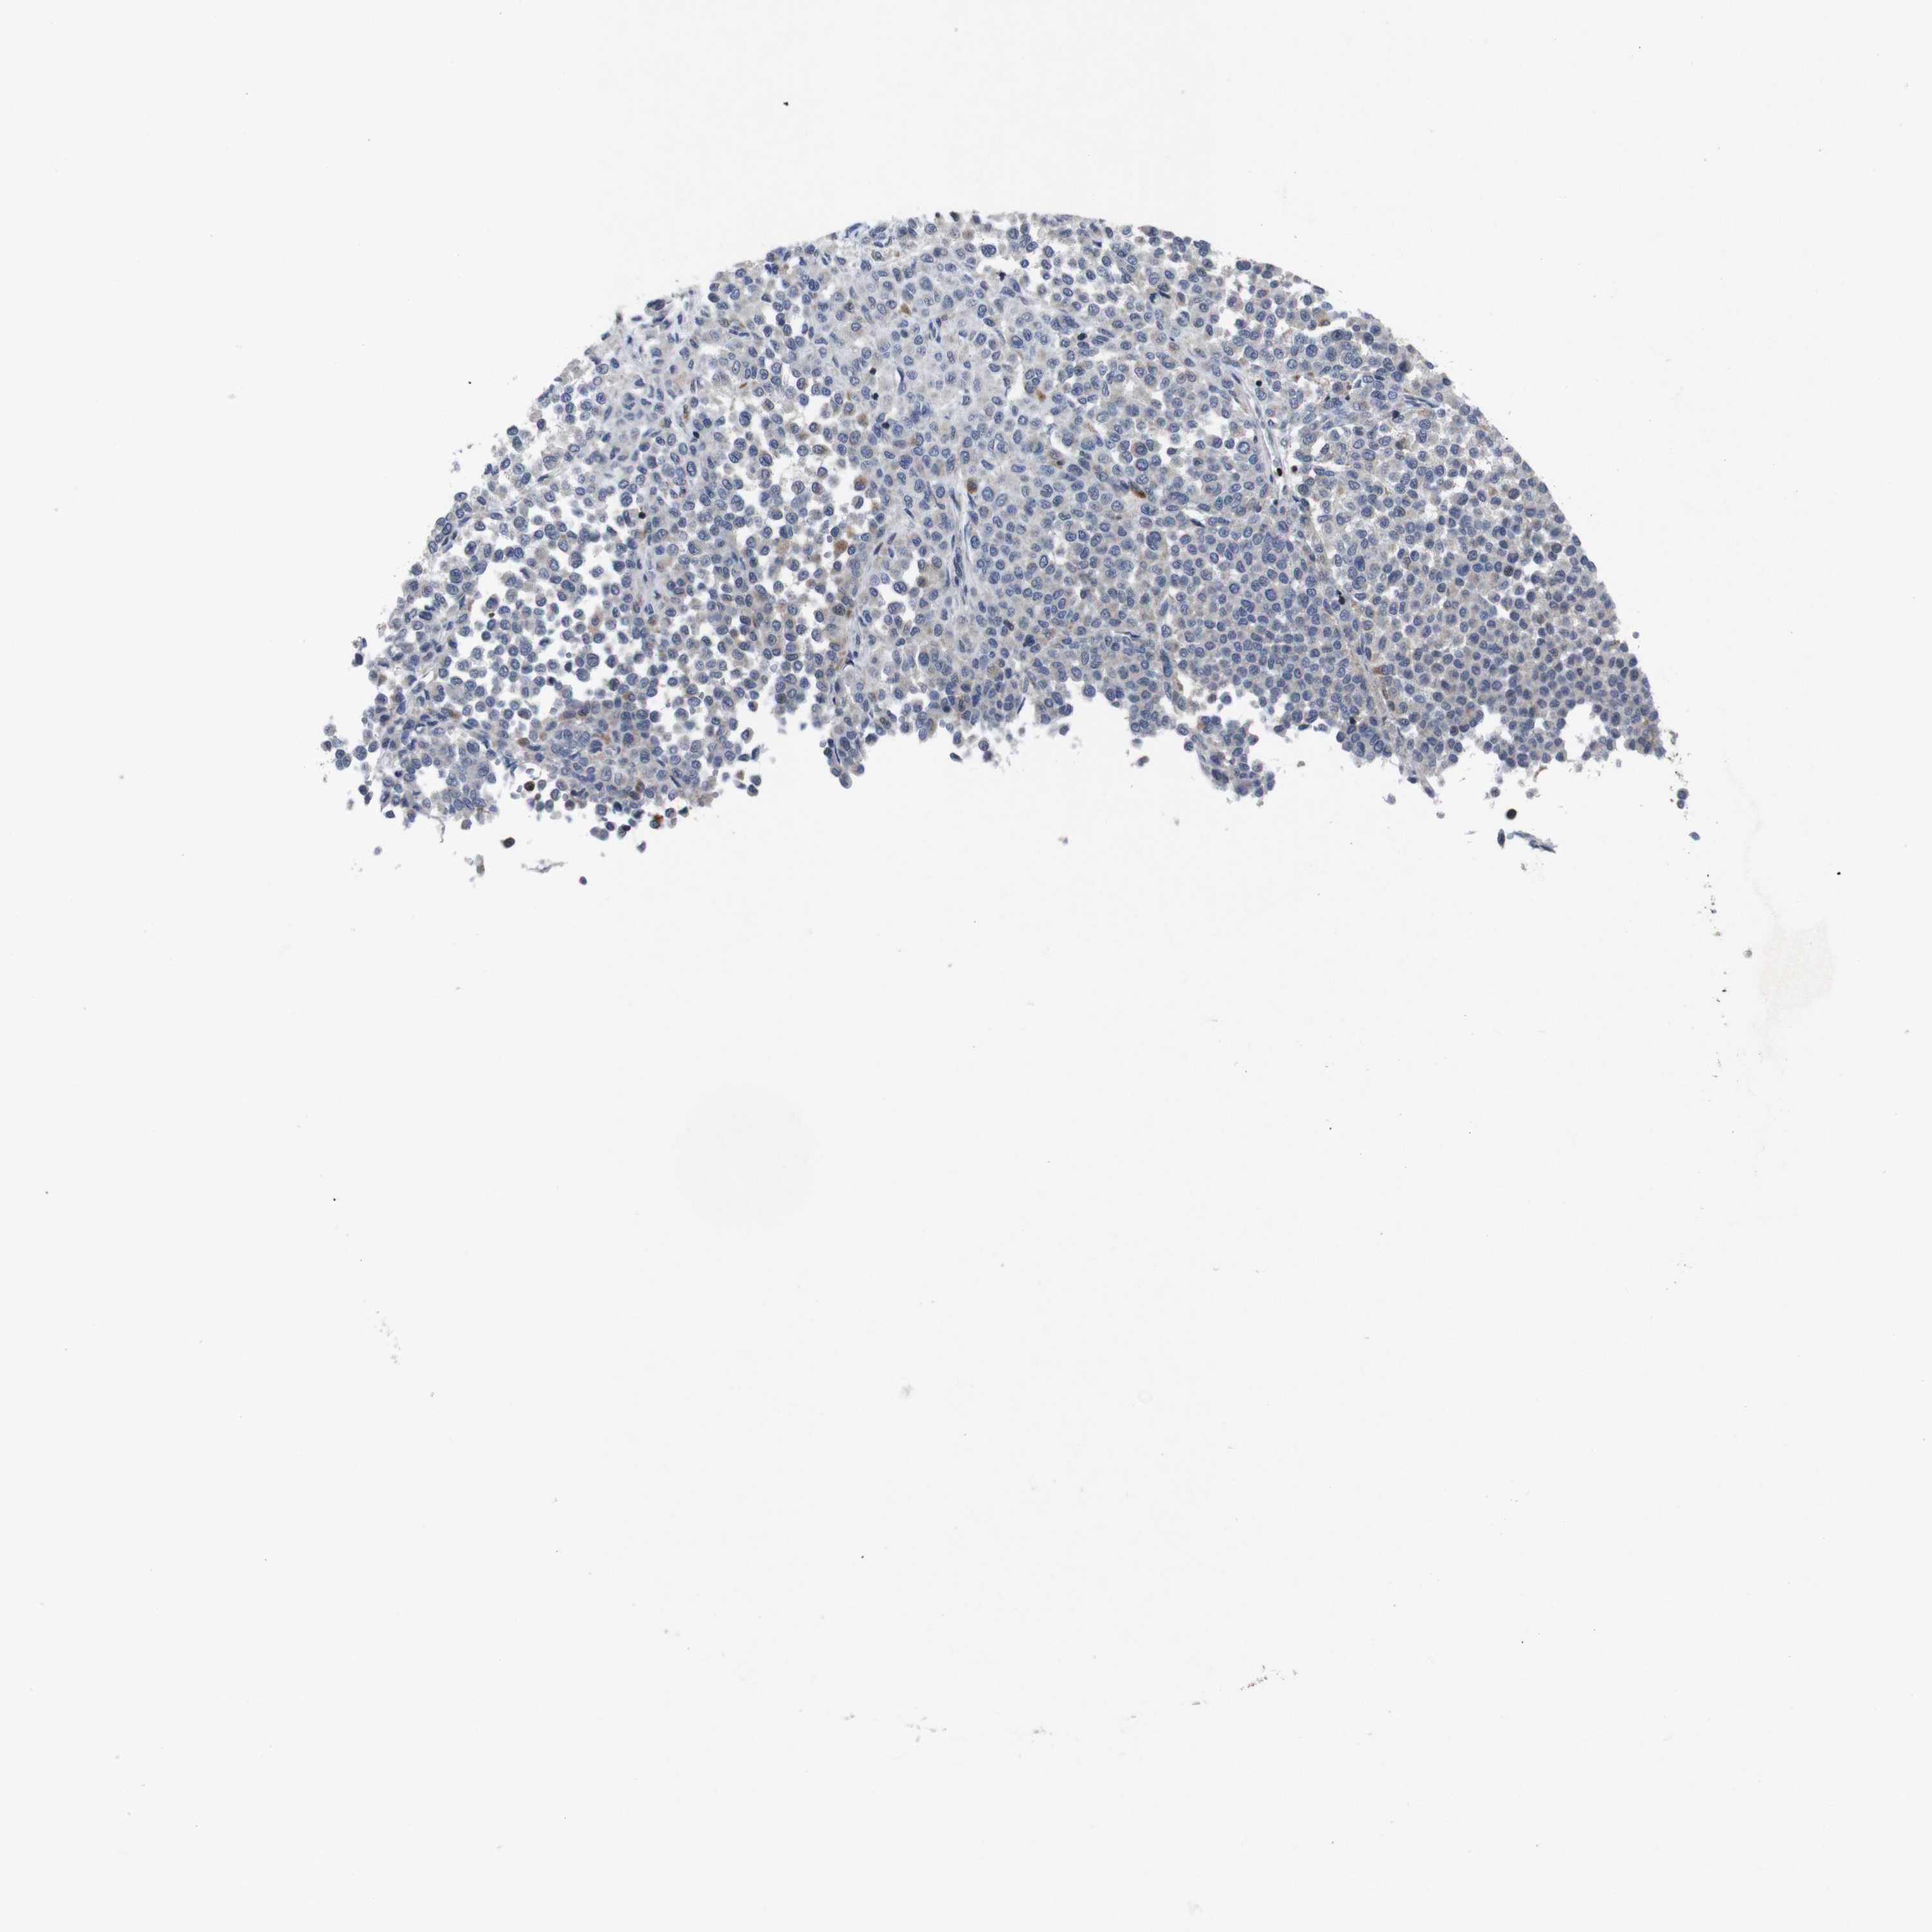

MELANOMA - Protein expressioni

A mouse-over function shows sample information and annotation data. Click on an image to view it in a full screen mode. Samples can be filtered based on level of antibody staining by selecting one or several of the following categories: high, medium, low and not detected. The assay and annotation is described here.

Note that samples used for immunohistochemistry by the Human Protein Atlas do not correspond to samples in the TCGA dataset.

Antibody stainingi

Antibody staining in the annotated cell types in the current human tissue is reported as not detected, low, medium, or high, based on conventional immunohistochemistry profiling in selected tissues. This score is based on the combination of the staining intensity and fraction of stained cells.

Each image is clickable and will lead to virtual microscopy that enables deeper exploration of all samples and also displays staining intensity scores, fraction scores and subcellular localization as well as patient and tissue information for each sample.

Antibody HPA001860

Antibody CAB013108

Staining

High

Medium

Low

Not detected

Intensity

Strong

Moderate

Weak

Negative

Quantity

>75%

75%-25%

<25%

None

Location

Nuclear

Cytoplasmic/membranous

Cytoplasmic/membranous,nuclear

Malignant melanoma, NOS

Malignant melanoma, Metastatic site